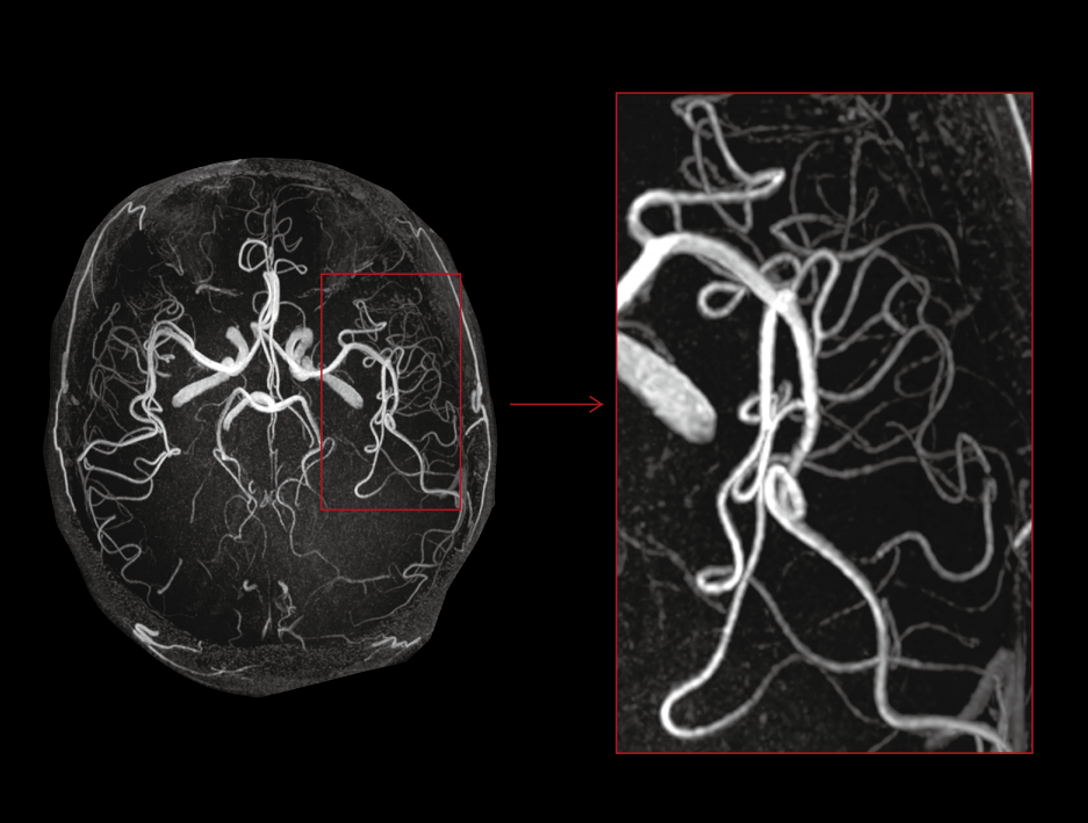

TOF

Plex brahial